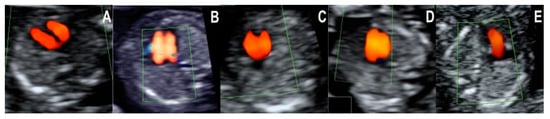

- Normal diastolic filling of both ventricles, with normal cardiac axis and two equally sized great vessels with normal antegrade flow, forming a V sign. This pattern was seen in all of the 20 cases with a structurally normal heart. The pattern’s negative predictive value for CHD that needs major surgical correction after birth is likely high, but little evidence is available to support this hypothesis. Isolated totally anomalous pulmonary veins return, and minor structural defects (e.g., ventricular septal defect, VSD), evolving lesions (e.g., mild valvular stenosis, tumors), or defects that are only postnatally diagnosed (e.g., atrial septal defect, ASD) might show this pattern in the first trimester.

- Common inflow of both ventricles through a common atrioventricular valve and two equally sized great vessels with normal antegrade flow, forming a V sign. All of the atrioventricular septal defect (AVSD) cases in our series showed this pattern in the first trimester. AVSD with situs solitus is usually associated with genetic disorders, namely Down syndrome [16,17].

- Filling of only one ventricle and one vessel with a straight course. The six hypoplastic left heart syndrome (HLHS) cases respected this pattern in the first trimester. The pattern was also seen in the one case of a univentricular heart from our collection. In the four-chamber view, only one ventricle (the right one in HLHS) has doppler inflow, while the other one is usually barely visible and has no doppler inflow. Correspondingly, in the three-vessel and trachea view, only one arterial vessel with doppler flow could be seen, namely the pulmonary artery with the ductus arteriosus in cases of a hypoplastic left heart. The prognosis of hypoplastic left heart syndrome, although not entirely predictable, is generally unfavorable, with no possibility of biventricular repair. The parents must be informed accordingly [1,18].

- Distinct filling of both ventricles, but the left ventricle appears shorter (smaller), and two unequal vessels form the V sign (one vessel narrower). All the four cases of coarctation of the aorta (CoAo) seen in the first trimester showed this pattern. This type of CHD is a progressive disease. In our experience, the cases suspected in the first trimester are usually severe.